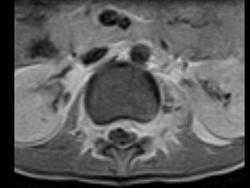

问题 女,9岁,背部隐痛,发热1个月余,MRI检查如图,请选出最可能的诊断 ( )

选项 A、脊椎结核伴硬膜外脓肿 B、椎体压缩骨折 C、脊柱转移瘤 D、硬膜下血肿 E、化脓性脊柱炎

答案 A